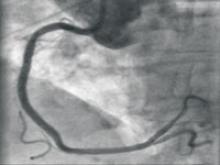

Canada is spearheading an international study to determine if an implantable cardioverter defibrillator (ICD) can prevent death from serious heart rhythm problems in those patients who’ve survived a heart attack. Heart disease is a leading cause of death in Canada and the fastest growing disease worldwide.